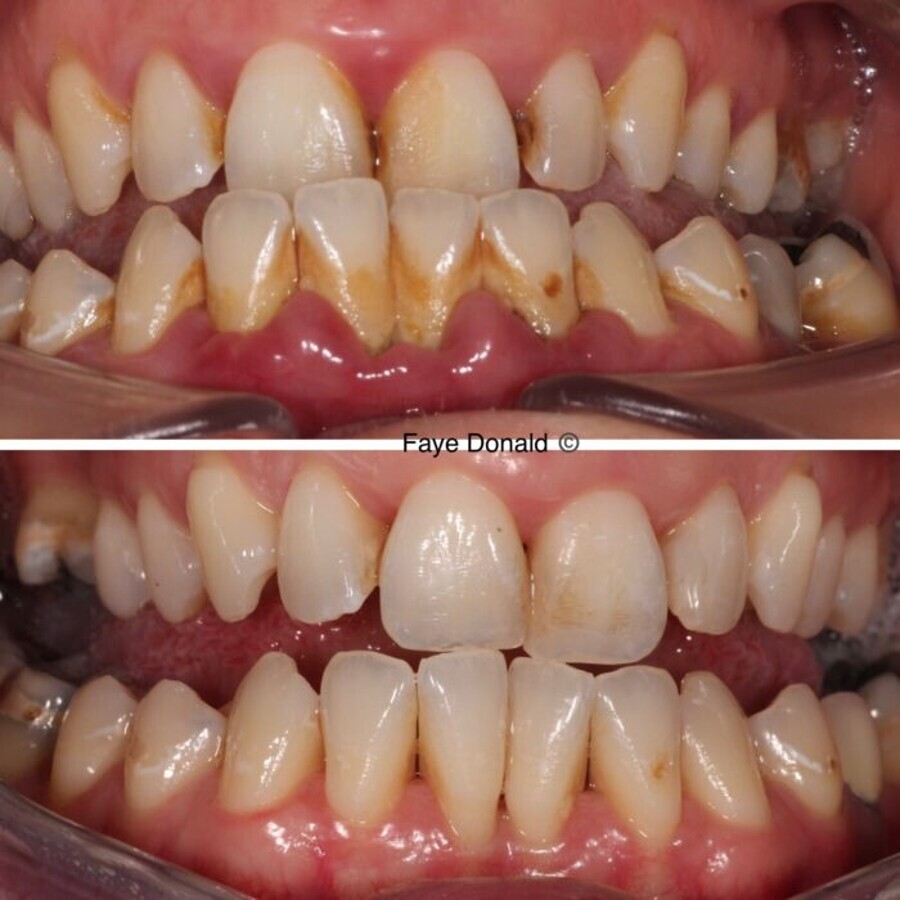

Upper – Initial presentation. Lower – 8 Weeks later

Appointment 3 (8 weeks later) The patient was again disclosed, and plaque and bleeding scores were taken. Both scores were recorded as <10% and a dramatic difference in appearance was noted. At this stage, a full-mouth periodontal chart was recorded. Anterior sextants showed no pockets >4mm and posterior sextants showed some shallow residual pocketing interdentally of between 4mm and 5mm with 3 sites measuring 6mm, one of which had bleeding on probing.

Post-appointment monitoring As the patient had displayed a good grasp of home care, motivation was excellent and early tissue resolution was extremely promising, a hands-off approach was applied to allow natural healing to continue. The patient was monitored closely at 12-week intervals for 1 year, during which her pocket chart revealed further resolution, with no site measuring >4mm and bleeding on probing remaining at <10%.